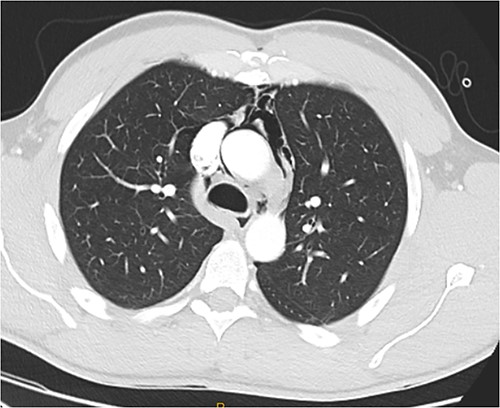

Following extubation, bilateral chest wall subcutaneous emphysema was noted extending to the neck. He also complained of central chest discomfort, without respiratory distress, oxygen desaturation or airway obstruction. Chest X-ray (CXR) revealed pneumomediastinum and surgical emphysema in the lateral chest walls bilaterally. Computed tomography (CT) of the chest, abdomen and pelvis demonstrated large volume subcutaneous emphysema bilaterally in the scrotum, abdominal and chest walls extending to the neck (see Figs 2–5). Gas was noted between the abdominal muscle layers, extraperitoneal and retroperitoneal spaces without pneumoperitoneum (see Figs 5–6). Moderate pneumomediastinum was prominent within the superior and antero-inferior mediastinum without evidence of tracheal or oesophageal injury and an associated small left pneumothorax was noted (see Figs 1–3).

CT chest coronal, pneumomediastinum and bilateral subcutaneous emphysema.